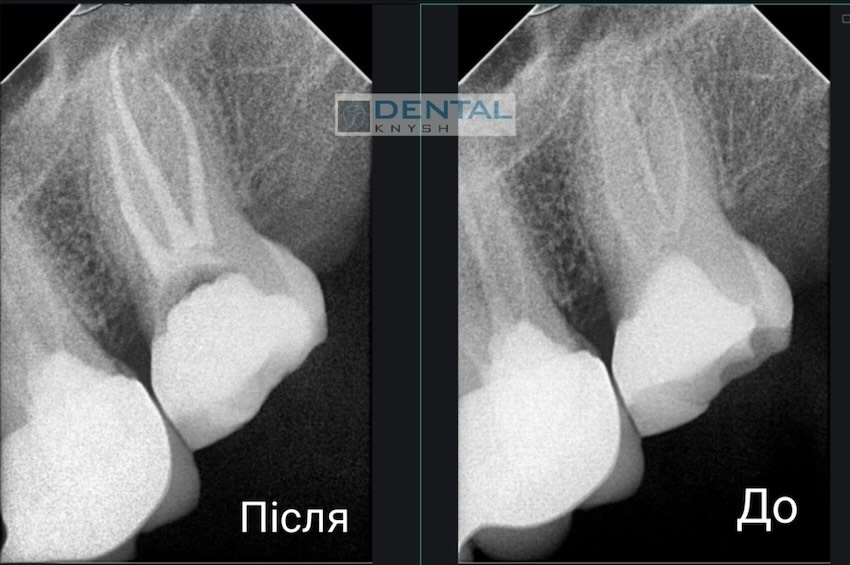

Лікар-ендодонтист Вадим Петриченко спеціалізується на лікуванні зубних каналів під мікроскопом.

Фото звіти

Більше фото звітів можна подивитися на сторінці Лікування зубів під мікроскопом